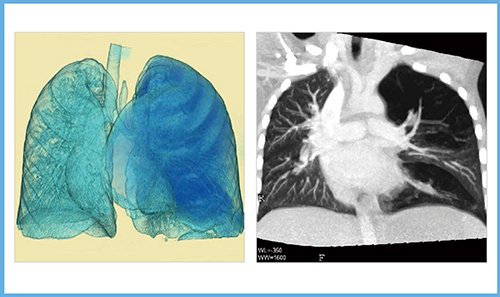

図4は,Aquilion ONEの1号機導入間もない頃に,ADCT指名で検査依頼された小児のスワイヤージェームズ症候群の画像である。当初はこれまでの経験から,呼吸同期による1回転のボリューム撮影を想定していた。しかし,ADCTではより確実な方法として一呼吸下での動態撮影が可能なことから,線量に注意して呼吸状態を観察しながらのダイナミック撮影に変更した。結果として,呼吸器の形態画像だけでなく,呼気と吸気の動態が把握でき,診断に寄与する情報を提供できた。従来のCTの経験則にとらわれず,ADCTという新しい概念への対応が必要だと実感した症例の一つである。

図4 ADCTの呼吸下ダイナミック撮影による小児スワイヤージェームズ症候群の画像